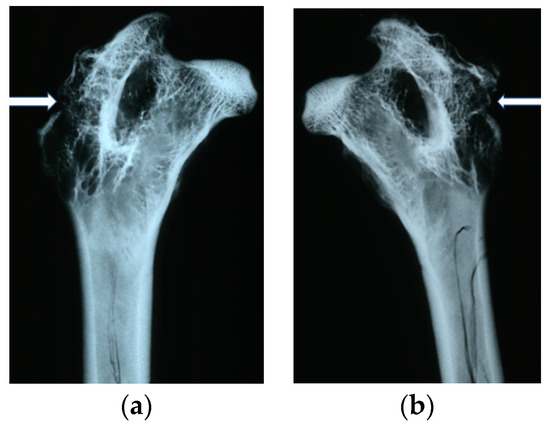

In X-ray imaging, all the implants remained translucent and invisible. At the first month after implantation, it was observed that the implant canals with implanted materials, PLGA + IGF1 and PLGA/PHB + IGF1, were partially filled with callus, which was partially sclerotic. In the implantation locations for the control materials, PLGA and PLGA/PHB, only traces of calluses were observed. All openings at the implantation sites were open. After two months, a continuation of filling with calluses was observed in the implant canals of the PLGA + IGF1 and PLGA/PHB + IGF1 samples. The implant holes remained open in the PLGA + IGF1 samples, while, in the PLGA/PHB + IGF1 samples, most holes were closed with osseous lamina. In individual control samples (PLGA/PHB), a marginal amount of osteosclerosis or osteolysis was observed. After three months, the implant canals were closed entirely or, in individual samples, partially closed with spongy calluses. In the PLGA implant materials, the implant canals were closed, except in some individual samples, in which the canals were partially filled with calluses from the bottom, while the entrances remained open. Six months after implantation, the implant canals were filled with spongy calluses. In individual control samples, trace osteolysis was recorded. All implant holes were closed by osseous lamina. In subsequent post mortem examinations (after nine to 12 months), the macroscopic images were similar. There were no periosteal reactions in the autopsy period. Radiographic images of changes within the groups are presented in Figure 4. The persistent differences between the control groups and the IGF1 tested groups are shown in Figure 5.

In the evaluation of the biocompatibility and bioactivity of the porous, fibrous bone implants of experimental PLGA + IGF1 and PLGA/PHB + IGF1 and control PLGA and PLGA + PHB, tests for allergenic reaction and tests for local bone tissue response after implantation for a period of one, two, three, six, nine, and 12 months were carried out. In the scheduled postmortem periods, macroscopic and radiological evaluations were performed, followed by microscopic histological evaluations of the healing process and the degradation time of the implanted materials. Our research revealed similar and correct clinical pictures for all types of implants. Every animal in both the experimental and control groups survived. The surgical wounds were healed by first intention. The animals retained active and passive mobility of the hip. Individual animals in the early period, one to two months after surgery, demonstrated slightly larger surroundings of the hip joint. During later periods, no change was noticed. Macroscopically, the soft tissues around the hip, following the implantation of all investigated implants, were correct and similar. During autopsy, moderate amounts of colourless exudate around the implant were observed in both the control group and the experimental group for individually tested animals one month after implantation. The macroscopic images of the experimental group and the control group in the early period showed the locations of the implantation on the trochanters’ surface. In subsequent periods, the implants were covered by periosteum and were barely visible. For individual animals from the experimental group (with a supplement of IGF1), a slight increase of femur trochanters was found in the macroscopic images; for the other animals, the shape and size of the trochanters were comparable to those in the control group. In X-ray imaging, all the implants remained translucent and invisible. Upon examination one month after implantation, the canals with PLGA + IGF1 and PLGA/PHB + IGF1 were partially filled with calluses, while, in those with control materials, only traces of callus were visible. After two months the implant holes remained open in the PLGA + IGF1 samples, while, in the PLGA/PHB + IGF1 samples, most of the implant holes were closed with osseous lamina. At later observations in all the groups the implant canals were filled with spongy calluses and closed by osseous lamina, partially after three months and entirely after six, nine, and 12 months. Compared to the control samples, those implanted with the tested materials were filled with thicker bone trabeculae.

Figure 5. Radiological images after implantation of the tested materials: (a) PLGA after six months. Traces of the implant channel are visible, filled with thin bone trabeculae. The implant channel is closed with a thin bone cap. (b) PLGA + IGF1 after six months. In contrast to the opposite side, the implant channel is invisible, filled with numerous thick bone trabeculae, and there is a thicker bone cap at the point of the borehole.

Molecules 22 01852 g005